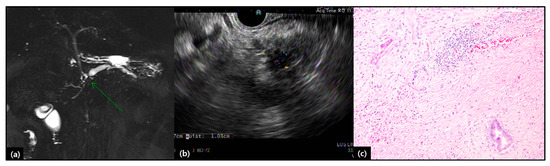

- Rho, S.Y.; Kim, J.S.; Chong, J.U.; Hwang, H.K.; Yoon, D.S.; Lee, W.J.; Kang, C.M. Indocyanine Green Perfusion Imaging-Guided Laparoscopic Pancreaticoduodenectomy: Potential Application in Retroperitoneal Margin Dissection. J. Gastrointest. Surg. 2018, 22, 1470–1474. [Google Scholar] [CrossRef]

- Choi, M.; Lee, S.J.; Shin, D.M.; Hwang, H.K.; Lee, W.J.; Kang, C.M. Laparoscopic repeated pancreatectomy for isolated local recurrence in remnant pancreas following laparoscopic radical pancreatectomy for pancreatic ductal adenocarcinoma: Two cases report. Ann. Hepatobiliary Pancreat Surg. 2020. Forthcoming. [Google Scholar]